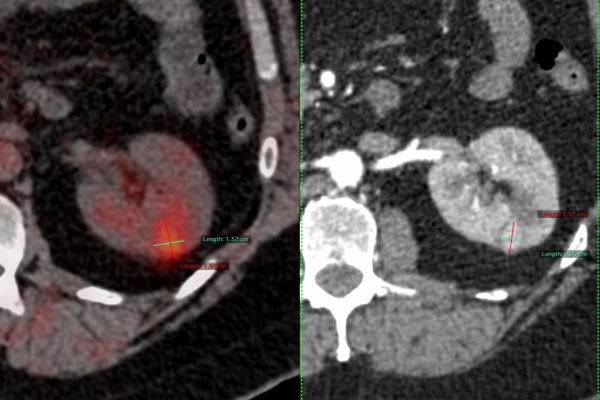

- Cancer Detection: Highlights tumours and measures their size and spread.